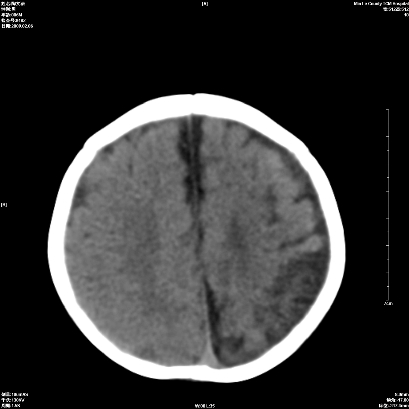

以下是引用wxq2008在2009-2-6 17:01:00的发言:[br]hie后遗症脑萎缩。

以下是引用学医在2009-2-6 21:45:00的发言:[br]hie后遗改变